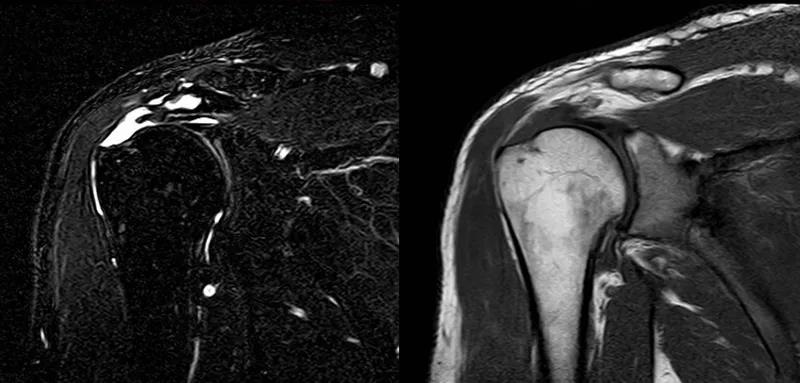

图21 斜冠状位(临床常用)a.T2,b.T1

图24 a.肩袖全层撕裂;b.正常MRI

图25 巨大肩袖损伤(冈上肌)